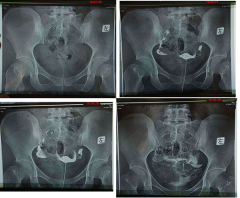

输卵管造影是通过导管向宫腔及输卵管注入造影剂,利用X线诊断仪行X线透视及摄片,根据造影剂在输卵管及盆腔内的显影情况来了解输卵管是否通畅。>>点击了解详情

(一)器械要求--500ma高精度X光机:

相比较于其它医院300ma的X光机,杭州红房子500ma高精度X光机有效度,专业医生熟练操作并并附以数字X光机的应用,医生可以观察到相关局部的情况,显示所有的软组织及活动情况,诊断相关的内部功能,清晰准。>>>输卵管造影检查疼吗?